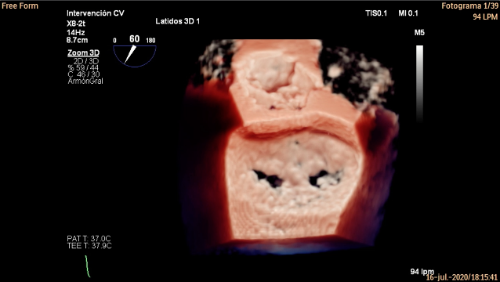

Imatge 3D i més seguretat

La sala d’operacions híbrida està equipada a més amb un ecògraf 3D dotat de programari TrueView d'última generació, que permet superposar la imatge ecocardiogràfica sobre l'obtinguda per RX: «Durant la intervenció cal que un ecografista expert, com el Dr. Alejandro Panaro de l'Institut del Cor Teknon, ens guiï pel que fa a la progressió dels dispositius a través de les càmeres cardíaques, posant atenció en aquest cas a les característiques anatòmiques de la vàlvula mitral per actuar amb la màxima precisió i optimitzar el resultat de la tècnica», afegeix el Dr. Dabit Arzamendi.